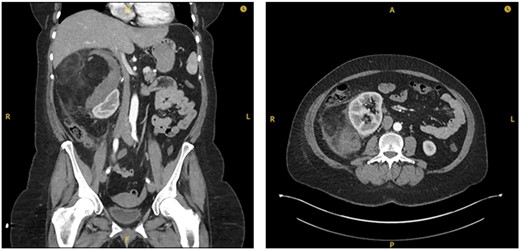

A 55-year-old Caucasian female presented to the emergency department (ED) after falling from sitting on a static pushbike onto her right flank. She immediately incurred right flank pain with nil other symptoms at time of the event. Her medical history was insignificant and she did not take any regular medications. Blood tests on admission indicated there may be an intra-abdominal injury due to raised lactate of 3 and a blood pH of 7.304. An urgent CT abdomen and pelvis (CTAP) with contrast was performed which showed a large (15.2×13.8 cm), predominantly fat containing mass in the right suprarenal region causing displacement of the right kidney and pancreas, with surrounding hyperdense fluid suggestive of acute retroperitoneal haemorrhage (Fig. 1).

Coronal (a) and transverse (b) sections of initial CT imaging with contrast showing large lesion with heterogeneous hypodense areas with surrounding haematoma (arrowed).